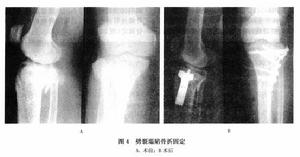

(6)脛骨平台骨折內固定:

③劈裂塌陷型骨折(Ⅲ型):先將劈裂骨折向外翻轉,顯露塌陷骨折片,用骨膜起子抬起塌陷骨折片復位,塌陷空腔植骨,再將劈裂骨折復位,用兩枚螺絲釘固定,對老年骨質疏鬆者亦可用L形和T形的支撐鋼板固定。